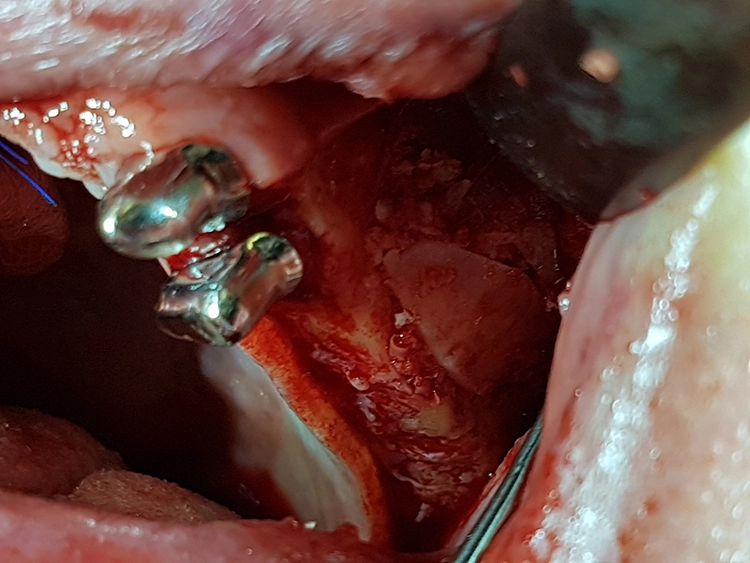

Bei der Elevation zeigte sich in regio 25 bis 27 eine Mund-Antrum-Verbindung (MAV), verursacht durch den parodontalen Knochenabbau. Da keine Anzeichen für eine Sinusitis vorlagen, wurde die MAV vor dem Verfüllen mit einer resorbierbaren, bovinen Kollagenmembran (Mem-Lok, BioHorizons Camlog) zur Kieferhöhle hin abgedeckt.

Apikal fixiert wurde die Membran durch das Verfüllen des Situs mit autologen Knochenspänen, retromolar aus regio 18 und 28 sowie 38 und 48 entnommen. Diese wurden jeweils zur Hälfte mit allogenem Knochenersatzmaterial (maxgraft, botiss biomaterials, Berlin) gemischt, womit eine natürliche Biofunktionalisierung des Knochenersatzmaterials erreicht wird.

Die präparierten Knochendeckel wurden in einer Kochsalzlösung zwischengelagert, um ein Austrocknen des entnommenen Knochens zu vermeiden. Nach dem Verfüllen konnten die Knochendeckel wieder passgenau in die Fenster repositioniert und das Weichgewebe vernäht werden.